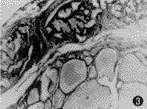

图3 甲状腺上动脉栓塞后病理切片,镜下见包膜下血管闭塞(血管直径325 μm×1 250 μm,250 μm×400 μm),滤泡上皮呈扁平或立方状(HE ×20)

9例伴巨大甲状腺的Graves病者,有6例于栓塞治疗2~3周后行双侧甲状腺次全切除,其中4例为外科手术前准备,栓塞目的是减少术中出血,有利于手术切除,2例介入栓塞治疗后症状好转,维持用药量减少,但甲状腺体积缩小不明显,患者要求手术切除治疗。本组手术切除病例使用的栓塞剂为明胶海绵或PVA,栓塞后甲状腺的病理改变相似,其栓塞后甲状腺病理改变(图3,4)所见为:闭塞的甲状腺上动脉首分支主干腔径为440~550 μm,下动脉首分支主干腔径为300~375 μm,其闭塞的细分支血管腔径为120~250 μm,未闭塞的末梢血管腔径为40~110 μm。峡部血管通过栓塞甲状腺上或下动脉亦可达到栓塞的目的。栓塞血管周围有异物性肉芽反应及纤维组织增生,栓塞血管腔内见多核巨细胞,动脉壁黏液变性、坏死及机化。甲状腺部分滤泡变小,滤泡上皮呈扁平、立方形,胶质减少,间质被纤维分隔并见淋巴细胞浸润及淋巴滤泡形成。但用明胶海绵栓塞的标本2周后可见部分血管再通。PVA颗粒大小不同所引起的病理改变略有不同:直径150~250 μm栓塞颗粒除栓塞细小动脉外,还明显引起腺体滤泡的变性、萎缩,直径350~400 μm栓塞颗粒仅栓塞较粗的分支动脉,细小动脉仍然部分通畅,部分出现血栓形成,腺体滤泡的变性、萎缩不如前者明显。